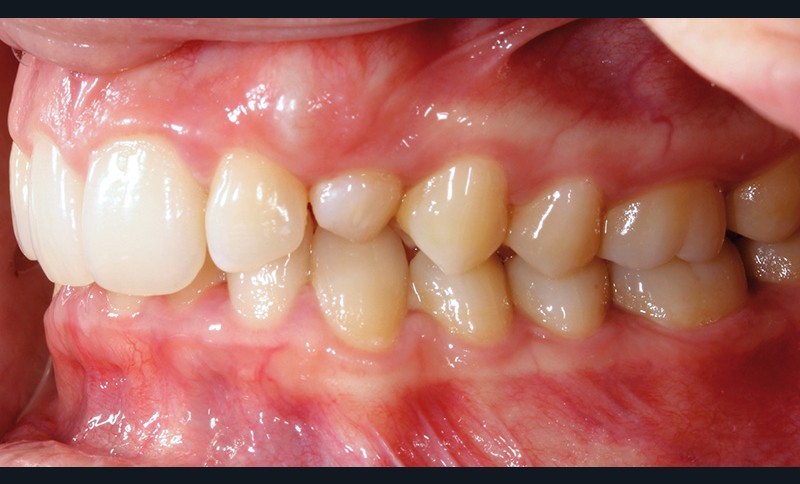

Aline se présente à la consultation pour une demande esthétique concernant ses deux canines lactéales qu’elle trouve trop petites et trop blanches (fig. 1a). Elle présente une classe II squelettique légère sur un schéma méso-divergent. D’un point de vue dentaire, une supraclusion est associée à une classe II d’Angle complète à gauche et de 4 mm à droite. Les canines maxillaires sont incluses (une vestibulaire et une palatine), avec persistance de leurs dents lactéales sur l’arcade (fig. 1b-h).

Un protocole orthodontico-chirurgical avec avancée mandibulaire est envisagé pour assurer un bon soutien labial, mais cette option est refusée par la patiente qui craint un visage trop carré. Concernant l’inclusion des canines maxillaires définitives, plusieurs thérapeutiques sont envisageables : 53, 63, 13, 23, ou 53, 63, 14, 24 peuvent être extraites, avec pour conséquence une classe II thérapeutique au niveau des molaires en fin de traitement. Cependant, la patiente souhaite mettre en place ses canines incluses pour conserver tout son capital dentaire et rétablir un idéal fonctionnel et esthétique au niveau des dents antérieures (fig. 2).